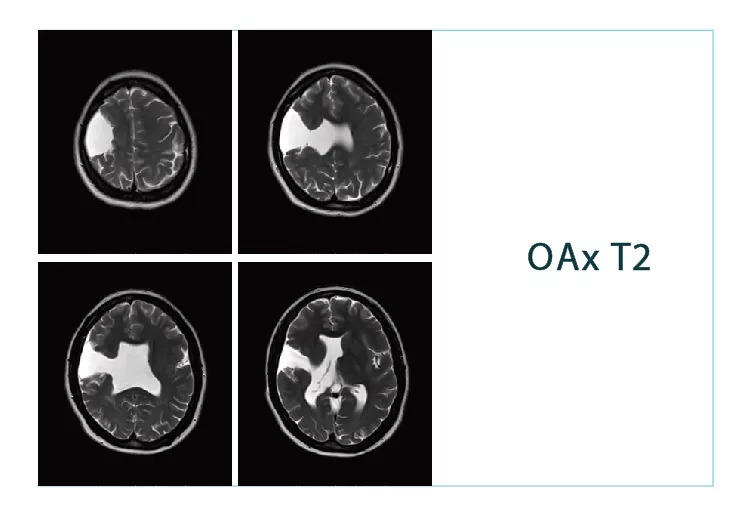

【朗润影像档案】20181102磁共振影像病例结果讨论